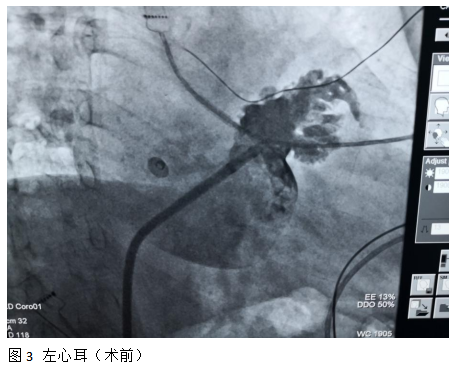

这例房颤患者系阵发性房颤,近期症状发作越来越频繁,每次持续时间也较前延长。发作时感觉心慌、头晕等不适。尤其是在一天之内不知何时发作,内心有不安甚至恐慌感觉,严重影响平日生活质量。几天前,患者来郑州九院心血管内科一病区进一步诊疗。经主管医师张国芳、高颖、刘小软以及病区袁清茹主任仔细评估诊断,和心脏中心主任赵明中博士共同讨论,并参考患者意愿,拟定冷冻球囊消融+左心耳封堵术“一站式”方案,于9月16日,在局麻下经过一站式微创介入方法达到了既改善症状、又降低卒中血栓风险的目的。

防治血栓栓塞一个是长期口服抗凝药,另外一个就是左心耳封堵。长期抗凝增加了出血风险,使很多房颤病人不能耐受,而非瓣膜性房颤90%以上的血栓形成于左心耳,国际前沿的先进技术左心耳封堵术就是封住房颤病人的血栓“老巢”,一劳永逸地既防治血栓栓塞症,又避免了长期抗凝药物带来的出血风险。